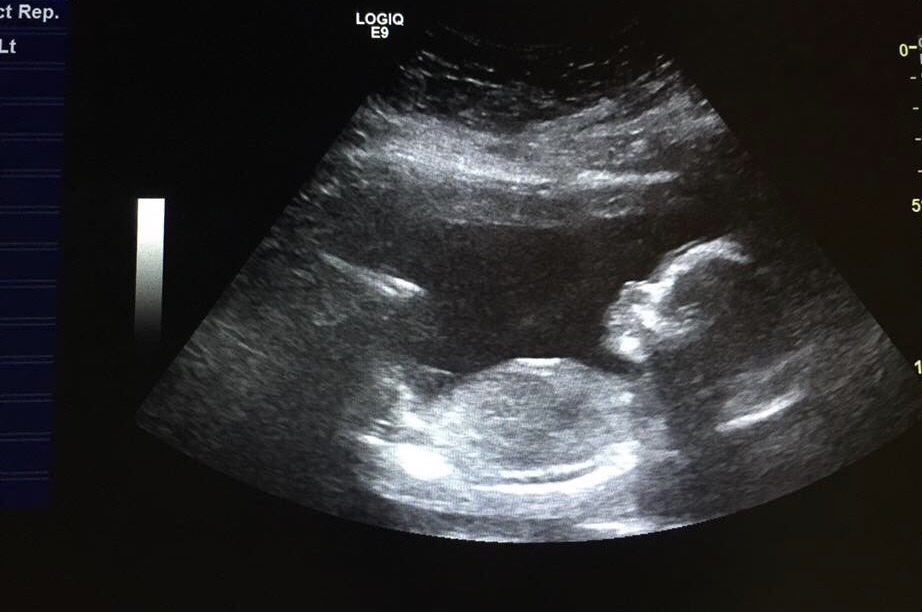

My friend wanted to be surprised by the gender but now wants to know. She asked me to look at it. And I think girl. But know you ladies are experts ! Thanks !Attachment 35737 this was at 20 weeks.

I'm not seeing any gender clues here. Does she have any 12-14 week side view shots? Or a potty shot, or video?

The skull looks slightly boyish, but it's not reliable.

What is the gestation? *. If I zoom in on the nub area I think I can see 2 lines which to me looks like a girly nub so my guess would be girl.

* sorry I've just noticed it says it's a 20 week scan pic under the pic - not sure if what I'm seeing is the nub or something else at this gestation ??